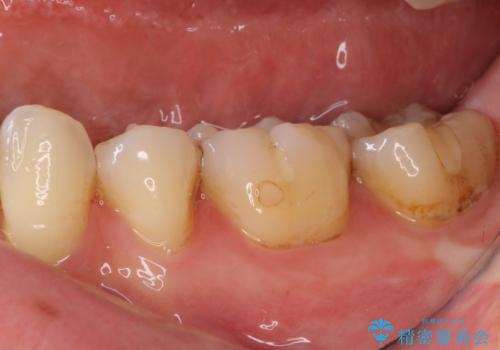

- 下の奥歯に虫歯ができてしまったとのことで来院された患者様です。

他にも気になる歯はありましたが、急を要する1歯のみをセラミックインレーにて修復治療を行うこととしました。

奥歯において、隣の歯と接触する部分に虫歯が及んでしまった場合、その場で充填を行う処置(コンポジットレジン修復)ですと、充填の縁に大きなギャップが生じてしまう可能性が高く、2次的な虫歯を引き起こすことになります。

また、処置した歯の後方にある歯は保険診療で使用するレジンインレーが装着されていますが、縁に虫歯が出来はじめていることが分かります。